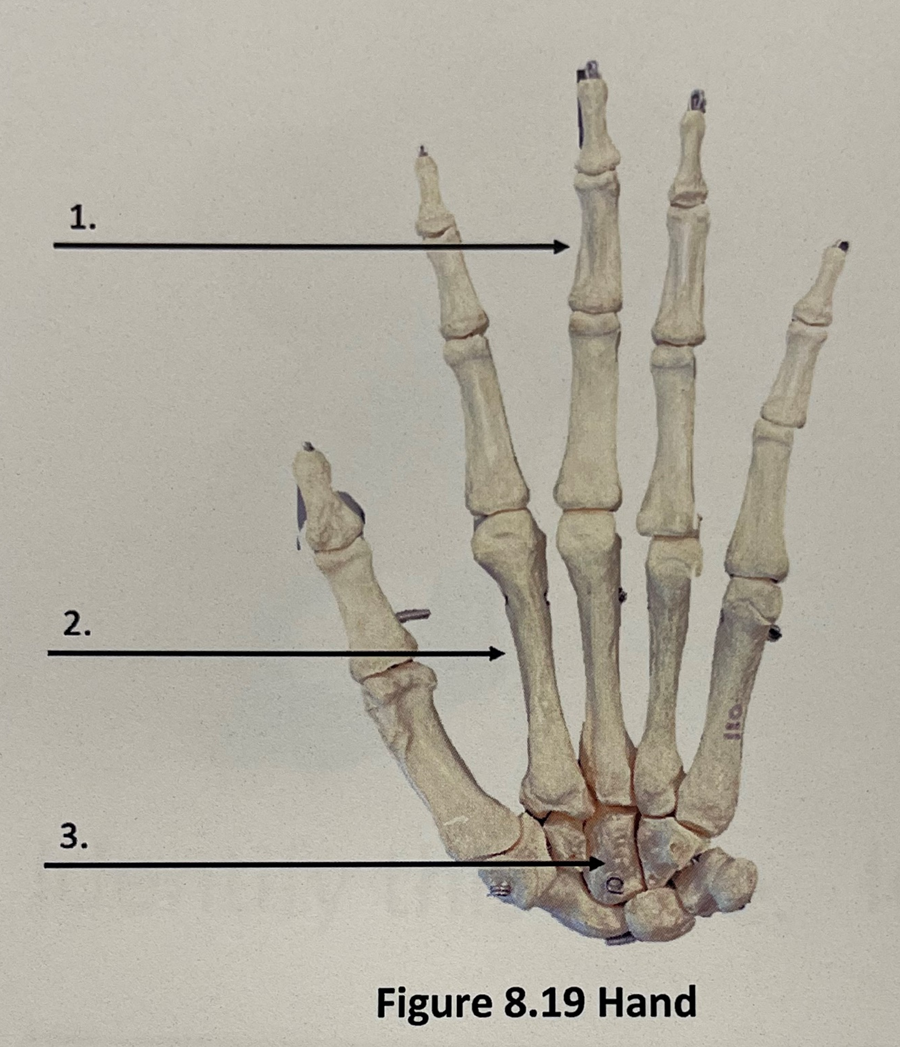

1

phalanges

2

metacarpals

3

carpals